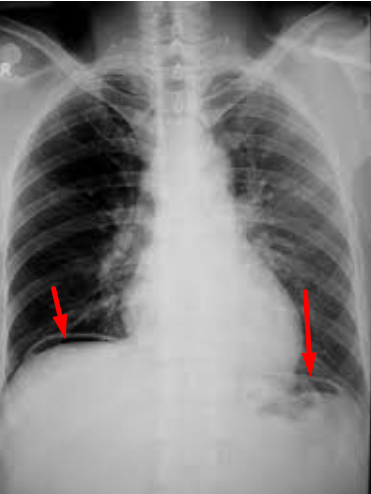

Hình 1.1. Hình khí tự do dưới cơ hoành (mũi tên đỏ) trước mổ của bệnh nhân Đ, chứng tỏ có thủng tạng rỗng

Bệnh nhân nam 15 tuổi, học sinh lớp 9 đang chuẩn bị thi cuối cấp lên lớp 10. Em có tiền sử viêm dạ dày tá tràng đã điều trị nội khoa nhiều đợt. Gần đây, lo lắng chuyện thi cử, luyện thi nên đau bụng vùng trên rốn nhiều hơn. Sau một ca học thêm buổi tối, em N.X.Đ về nhà thì bị đau bụng dữ dội kèm theo sốt cao. Em Đ được gia đình đưa vào Bệnh viện Bạch Mai cấp cứu trong tình trạng có hội chứng nhiễm trùng rõ, bụng đau co cứng như gỗ. Sau khi được làm những xét nghiệm cần thiết, bệnh nhân Đ được chẩn đoán: Viêm phúc mạc do thủng ổ loét hành tá tràng. Ngay sau đó, bệnh nhân Đ được các bác sĩ mổ cấp cứu phẫu thuật nội soi khâu lỗ thủng ổ loét hành tá tràng, lau rửa, dẫn lưu ổ bụng. Bệnh nhân Đ được ra viện sau 5 ngày điều trị nhưng vẫn phải tiếp tục điều trị thuốc và theo dõi khám lại.